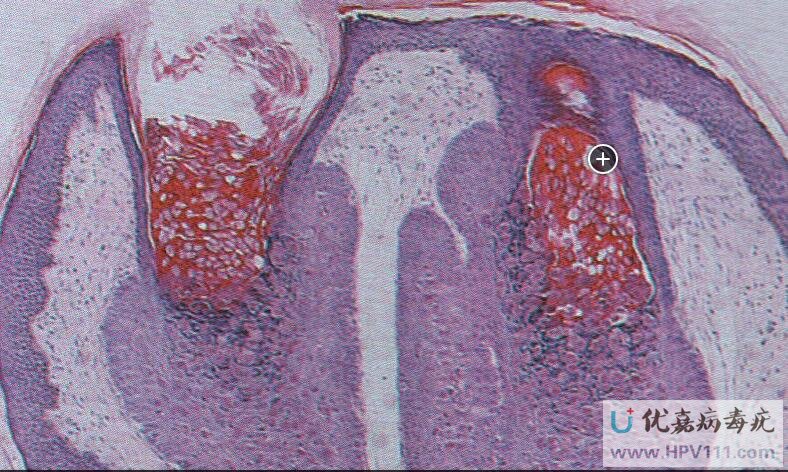

典型的组织病理学表现为增生的表皮上出现一个充满软疣小体的火山口外观。软疣小体为一种大型(可达35μm)、离散的卵圆形浆内包涵体,外观似大型嗜酸性颗粒团,可将细胞核和大量角质颗粒推到细胞一侧。

传染性软疣,表皮增生,真皮乳头将其分隔为多个倒置的梨形小叶。棘细胞增大,细胞质内有嗜伊红性包涵体(软疣小体)。

传染性软疣病理改变:表皮中部细胞内大的嗜伊红性包涵体(软疣小体)箭头所示,几乎占据整个表皮细胞,细胞核被压缩成新月状,位于细胞边缘,甚至消失。